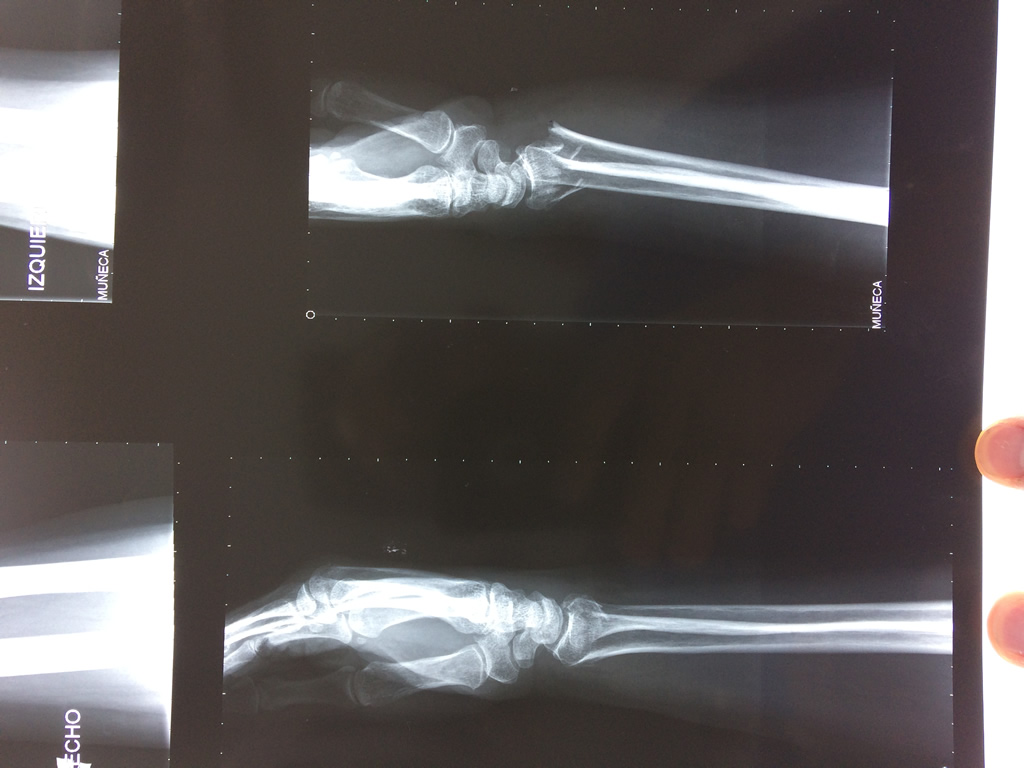

Cirugías de Calcaneo - Cirugías de Muñecas y Manos

Los procedimientos más comunes en cirugía de la mano son aquellos destinados a reparar traumatismos, incluyendo lesiones de tendones, nervios, vasos sanguíneos, y articulaciones; huesos fracturados; y quemaduras, cortes, y otros daños de la piel.